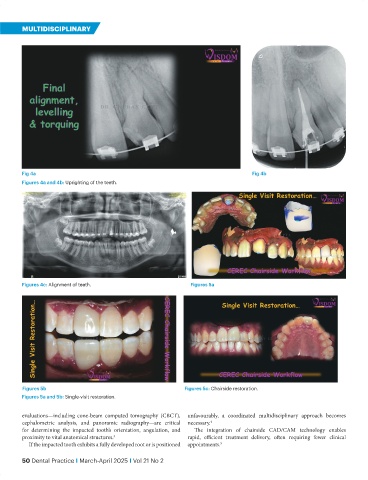

Fig 4a Fig 4b

Figures 4a and 4b: Uprighting of the teeth.

Figures 4c: Alignment of teeth. Figures 5a

Figures 5b Figures 5c: Chairside restoration.

Figures 5a and 5b: Single-visit restoration.